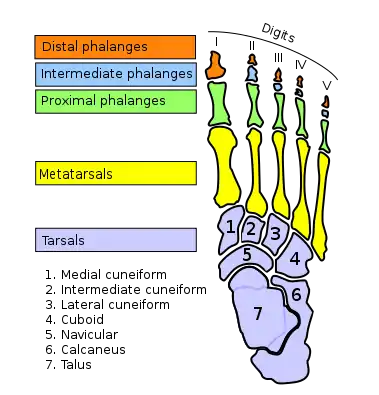

In humans and many other primates, the calcaneus (/kælˈkeɪniəs/; from the Latin calcaneus or calcaneum, meaning heel[1]) or heel bone is a bone of the tarsus of the foot which constitutes the heel. In some other animals, it is the point of the hock.

In humans, the calcaneus is the largest of the tarsal bones and the largest bone of the foot. Its long axis is pointed forwards and laterally.[2] The talus bone, calcaneus, and navicular bone are considered the proximal row of tarsal bones.[3] In the calcaneus, several important structures can be distinguished:[3]